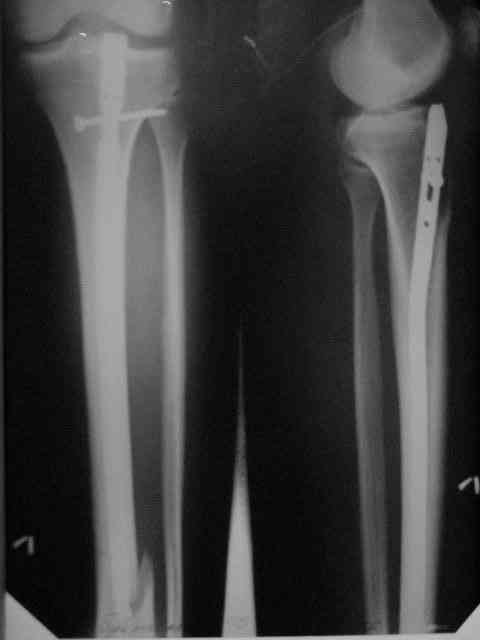

Здравствуйте коллеги! Больной 29 лет поступил 1 мая с Диагнозом: Закрытый спиральный перелом н/3 большеберцовой кости, перелом в/3 малоберцовой.

На пятые сутки выполнен вот такой остеосинтез (см R-gr) . На сегодня мы имеем перелом нижнего винта, замедленное сращение( R- gr от 11.09.06) Больного ничего не беспокоит, ходит с костылями с ограниченной нагрузкой. На наш взгляд возможно обойтись :1 Удаление сломанного винта и верхнего блокирующего с последующим более глубоким погружением штифта и его дистальным блокированием. Либо замена на более длинный (Экперт-Синтез).2 Остеотомия косая малоберцовой кости. С большим вниманием выслушаем возможные варианты, тактики в таком случае. С Уважением Владимир Бахарев. P.S Извинямси за качество снимков!